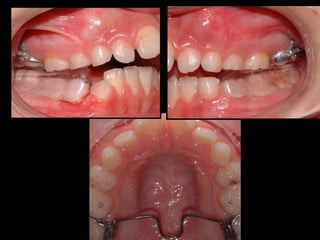

ACTIVACIÓN DE ROTACIÓN DISTAL INSTALAR LA BARRA DE UN LADO EL OTRO EXTREMO DEBE QUEDAR 5MM POR DISTAL DEL TUBO CONTRARIO

LA ACTIVACIÓN  ES CORRECTA CUANDO LA LLAVE LIBRE  SE DESPLAZA  5MM  POR DISTAL DEL TUBO OPUESTO

ACTIVACIÓN DE ROTACIÓNDISTAL INSTALAR LA BARRA DE UN LADO EL OTRO EXTREMO DEBE QUEDAR 5MM POR DISTAL DEL TUBO CONTRARIO